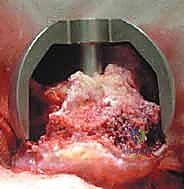

5. تحضير وتلبيس تجويف الحُق (Acetabular Component)

يتم تنظيف تجويف الحوض (الحُق) من الغضاريف المتآكلة باستخدام مبشرة طبية، ثم يزرع وعاء معدني (Cup) داخل التجويف. هذا الوعاء يثبت عادة عن طريق الضغط (Press-fit) حيث ينمو العظم الطبيعي لاحقاً حوله ليثبته بقوة.